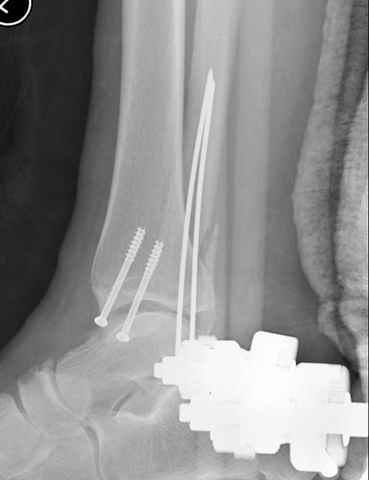

Второй случай сделан из одного разреза

На прямой проекции послеоперационного Рг макроскопически все выглядит очень анатомично, при микроскопическом ( :-)) ) рассмотрении можно все-таки заметить вальгизацию тарана, суставная щель в латеральном отделе сустава несколько уже , чем в медиальном при отсутствии латерального смещения тарана. У меня был аналогичный случай (без LISS , без мини доступа) с вальгусным наклоном тарана при восстановленном ankle mortise при последовательном наблюдении с интервалами в 6-8 недель в послеоперационном периоде отмечалось прогрессирующее сужение суставной щели в латеральном отделе сустава, закончившееся посттравматическим ОА, к счастью боли умеренные, купируемые аналгетиками или своими эндорфинами:-))(активная пациентка, у которой нет времени на болезни....) Какова жизненная ситуация в приведенном вами случае? И последнее, что я хотел бы прояснить для себя - фиксация внутренней лодыжки: я обычно комбинирую фиксацию компрессирующим винтом со спицей - по идее ротационная стабильность должна быть лучше, чем один винт, каковы ваши наблюдения в этом плане?

Pilon fracture:

конец малоберцевой кости, к нему прикрепляется латеральный суставной фрагмент дистального эпиметафиза большеберцовой кости (как на снимке)

и таранная кость, которые при репозиции малоберцовой кости репонируются автоматически.